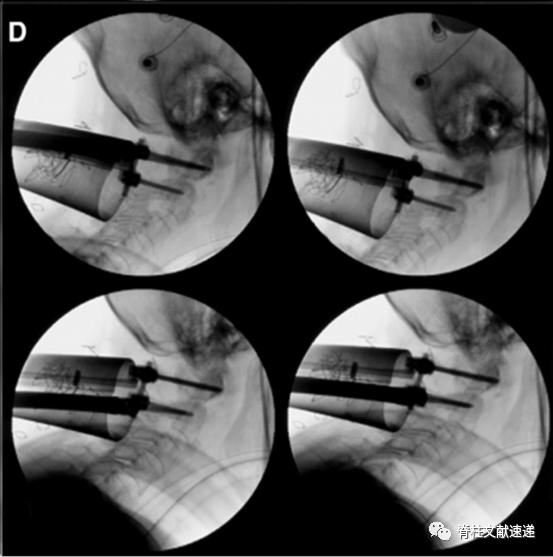

该作者首先进行了4例尸体试验,然后对2例II型齿状突骨折患者进行了微创通道下寰枢椎固定术。下图为一组术中透视影像。

上图:初级扩张通道定位于C2侧块,逐级扩张。

上图:探查C1/2侧块间隙,作出C2椎弓根螺钉钉道。

上图:作出C1侧块螺钉钉道。

上图:完成寰枢椎固定。